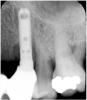

Figure 4 Radiograph of site No. 12 manifesting alveolar bone loss that is associated with an infection. (Radiograph courtesy of Dr. John Cavallaro.)

Figure 4

Figure 3 Clinical view of site No. 12 demonstrating pus upon palpation. Pus can be different colors. Not all infected sites manifest pus. (Photograph courtesy of Dr. John Cavallaro.)

Figure 3